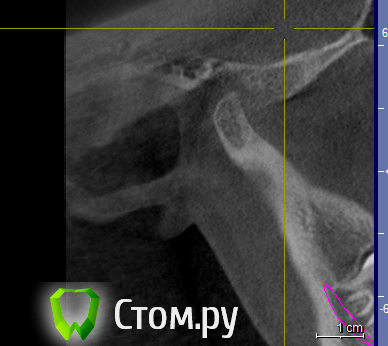

ElenaV Опубликовано 29 июня, 2014 Поделиться Опубликовано 29 июня, 2014 (изменено) Здравствуйте, дорогие доктора! У моей дочери 16ти лет проблема с ВНЧС. При ношении брекетов ей вытягивали нижнюю челюсть, выравнивали прикус и зубы , в частности - клыки выпирающие выравнивали. А через 1,5 года после снятия в одно прекрасное утро не смогла открыть рот. Нам советовали делать лазер, становилось легче. Так было 2 раза. А теперь по утрам, если спит на правой щеке, то челюсть правую заклинивает. Голова сильно болит в висках. Связано ли это с брекетами или другая причина может быть? У нас в Красноярске мы нашли доктора, который собрался нам помочь, поставить шины http://astreja.ru/uslugi/neyro-myshechnaya-stomatologiya. Может ли шина помочь решить эту проблему? В Красноярске выбор докторов небольшой, можно сказать - его нет. И уже просто страшно становится. Читая в интернете об этой проблеме, поняла, что это дело очень тонкое и непростое, испортить жизнь ребенку можно запросто. А еще советуют мануального терапевта. Куда пойти ? Может ли мануальный терапевт решить эти проблемы? Знакомый стоматолог сказал, что если челюсть поправят, то прикус может нарушится. А мануальный говорит - приходите - все исправим, даже снимков ему не надо. Теперь хочу выяснить у специалистов, как все таки поступить. К кому пойти сначала. Очень Вам буду благодарна за совет.Дорогие доктора, можете подсказать, что с суставом? Доктор сказал, что сустав находится далеко от височной кости, т.е. расстояние больше чем норма. Напишите, пожалуйста, что Вы видите на снимке, какую патологию. Вот еще сделала скриншоты суставов: левый и правый Вот еще правый сустав, немножко по другому Изменено 29 июня, 2014 пользователем ElenaV Ссылка на комментарий

Skip Опубликовано 29 июня, 2014 Поделиться Опубликовано 29 июня, 2014 Напишите, пожалуйста, что Вы видите на снимке, какую патологию. Эти КТ, с полуоткрытым ртом и выдвинутой челюстью, мало о чём говорят. У вас там что, уже стоит шина? Ссылка на комментарий

ElenaV Опубликовано 30 июня, 2014 Автор Поделиться Опубликовано 30 июня, 2014 (изменено) Эти КТ, с полуоткрытым ртом и выдвинутой челюстью, мало о чём говорят. У вас там что, уже стоит шина?Шины еще нет, мы сходили на прием, советуют ставить шину. Это КТ в 3Д делали с пластиной во рту, сказали - так надо. Что обычно так делают.Может поэтому и кажется доктору, что сустав неправильно в лунке стоит? Доктор сказал, что сустав далеко стоит от нормального местоположения. Поэтому выскакивает.Нужно МРТ сделать что бы точно понять? Или КТ переделывать? Изменено 30 июня, 2014 пользователем ElenaV Ссылка на комментарий

Force Опубликовано 1 июля, 2014 Поделиться Опубликовано 1 июля, 2014 с восковым шаблоном это по Маклафлину в ЦС сделано КТ. 1 Ссылка на комментарий

Skip Опубликовано 1 июля, 2014 Поделиться Опубликовано 1 июля, 2014 с восковым шаблоном это по Маклафлину в ЦС сделано КТ. Понятно. Ну тогда и с привычной окклюзией стоило бы сравнить, т.е. два снимка, а вернее три, если добавить макс. открытие рта. 1 Ссылка на комментарий